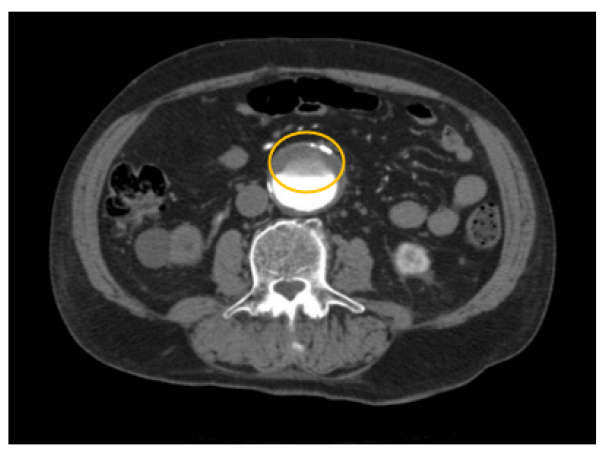

Cerebral Hemorrhage Connected to Alveolar Echinococcosis: An Exceptional Case

Khalid Al Taha, Alda Rocca, Philippe Maeder and Jocelyne Bloch. 15(5): 93-99.